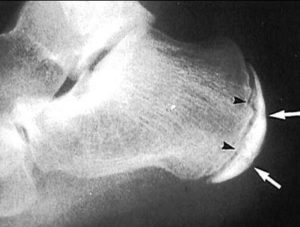

- Рентгенография в боковой проекции стопы.

На рентгеновском снимке врач может обнаружить фрагменты осколков кости, очаги формирования губчатой структуры, однородность состава окостеневшего ядра.

Эти методы помогают отличить болезнь Шинца от идентичных патологий – туберкулеза костной ткани, бурсита, периостита, остеомиелита, ахиллобурсита и некоторых других болезней.